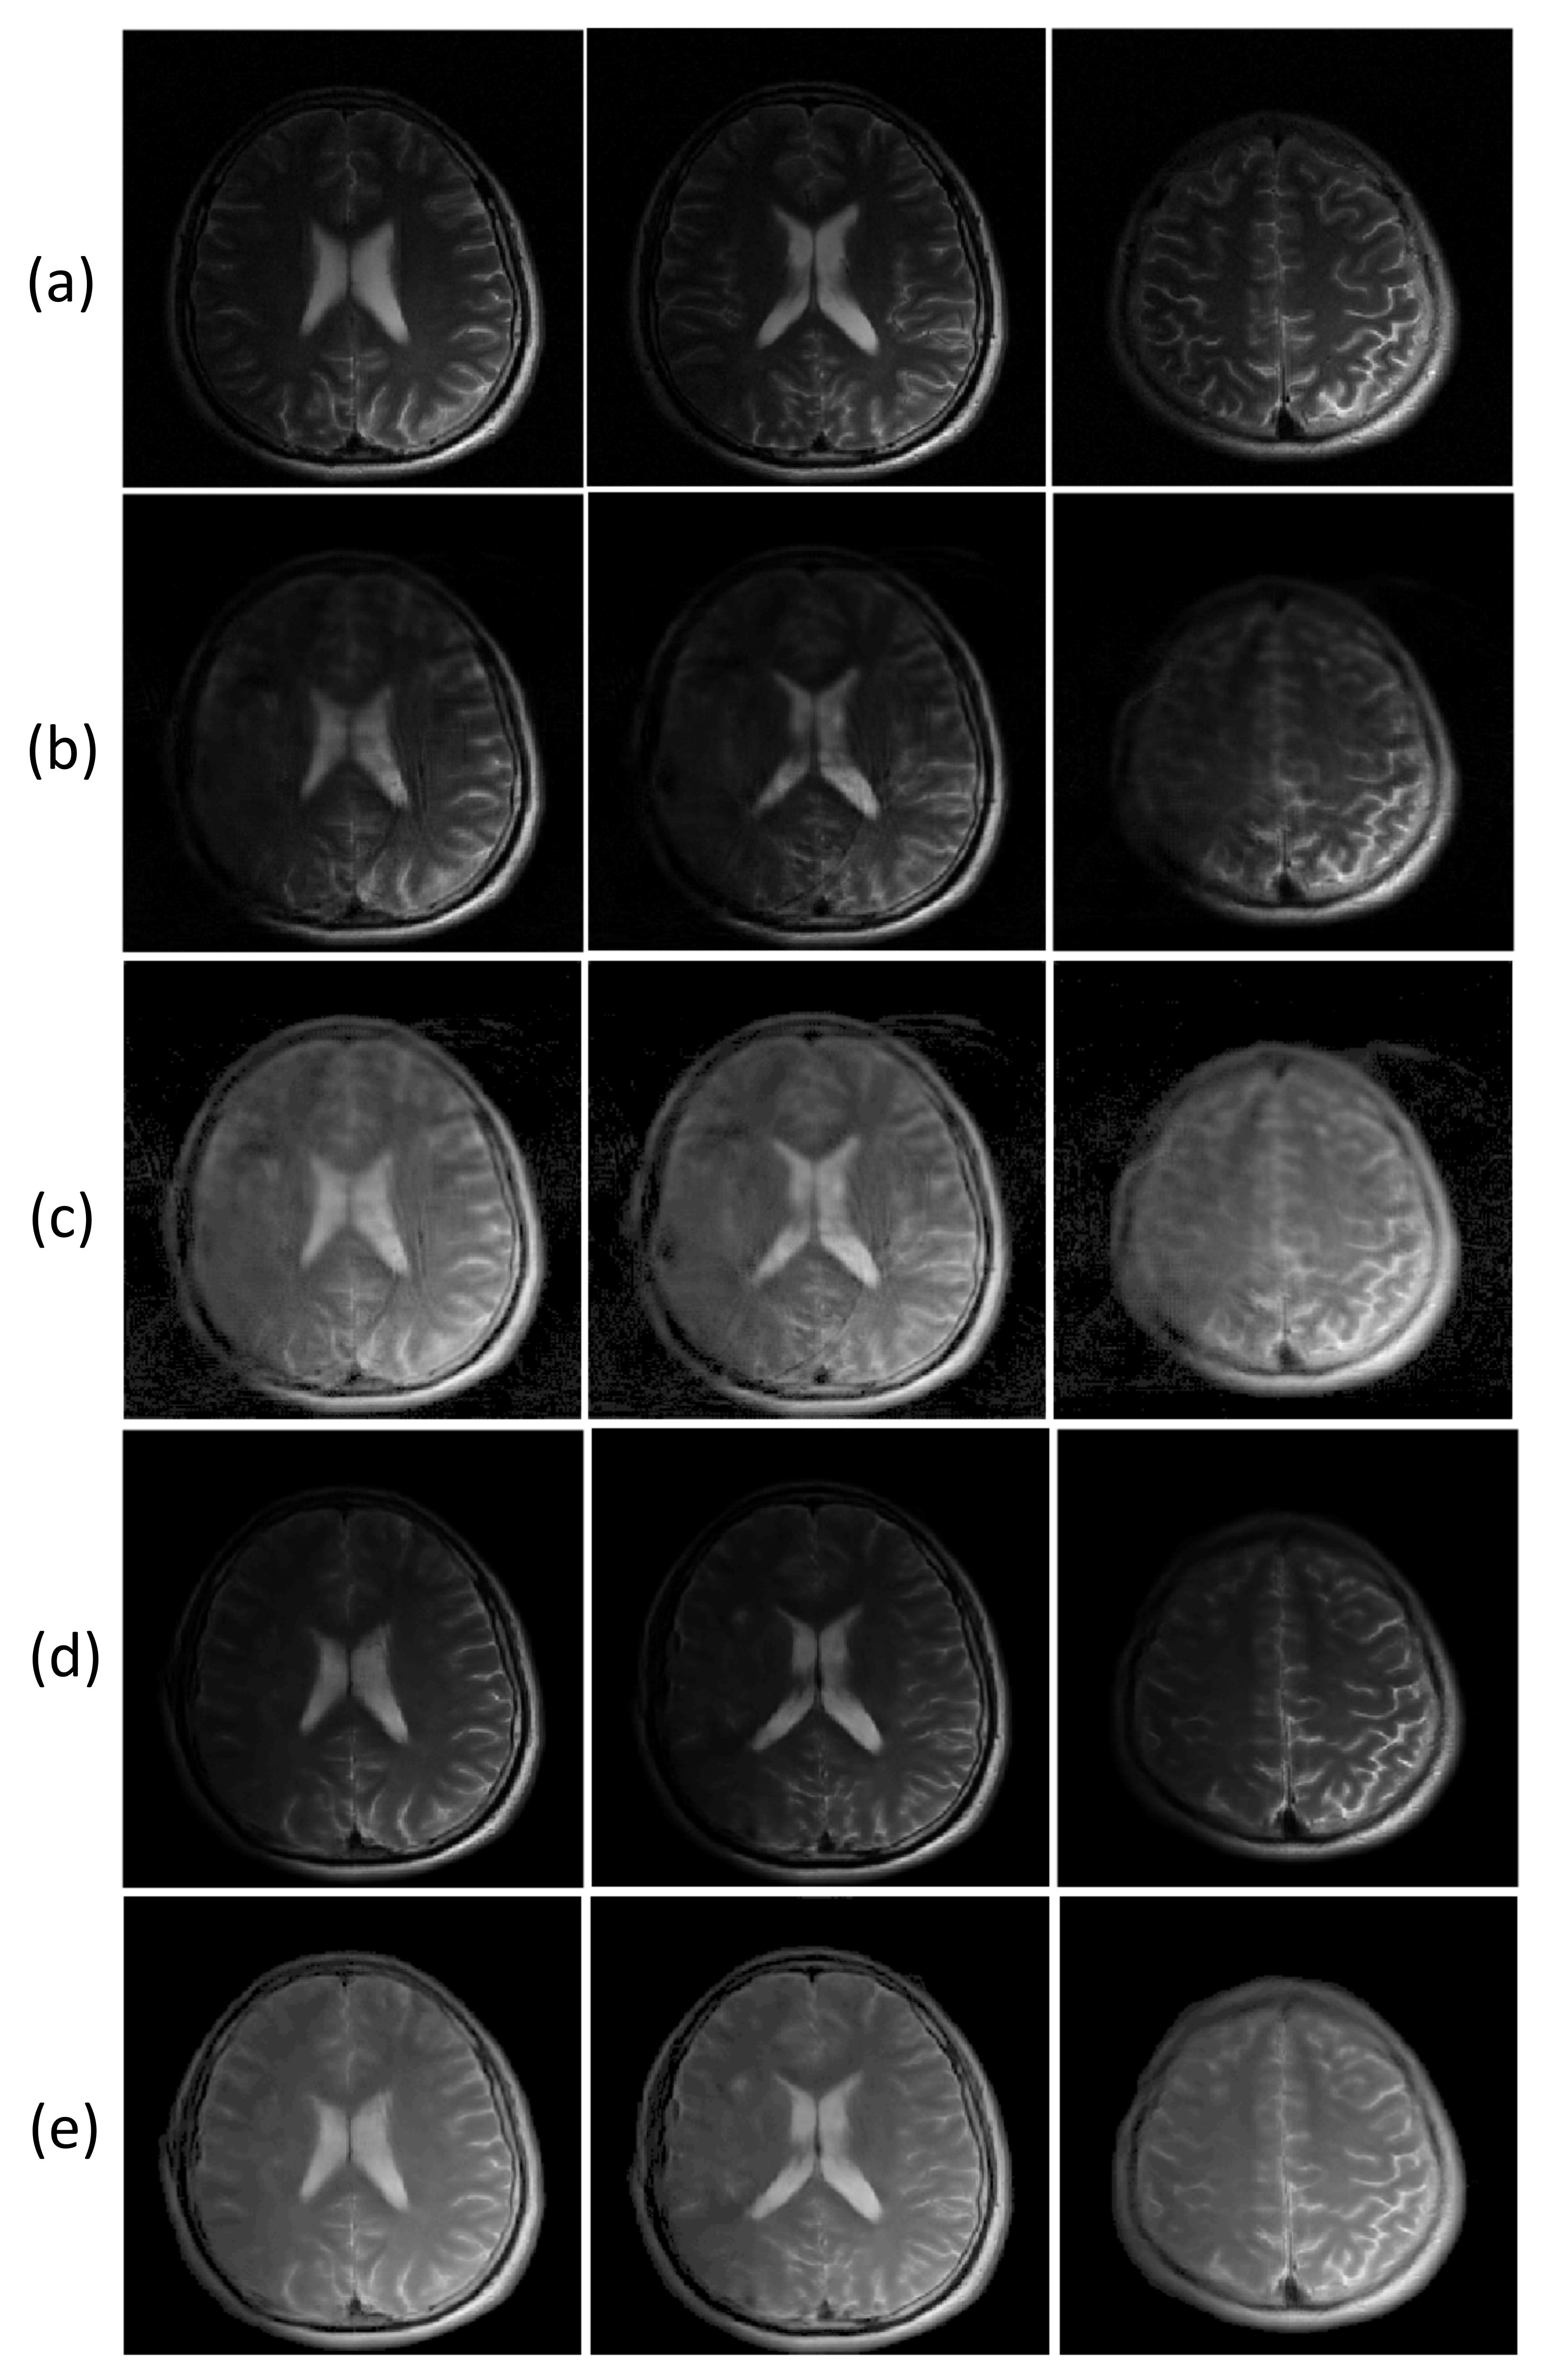

While most parallel MRI methods utilize information from multi-channel RF coils to reconstruct images from undersampled k-space data, deep learning-based reconstruction approaches can generate unaliased images from an undersampled dataset without using the information of the multi-channel receive coil [40]. To demonstrate the performance of the proposed ETER-net, we performed image reconstruction from the undersampled k-space data obtained with a single receive channel. To compare the results with a commonly used deep learning reconstruction method, we also simulated the image-domain to image-domain reconstruction using the dual frame U-net. In this experiment, the label images were reconstructed from fully sampled k-space data of a single receive channel. Figure 6 shows three different slices reconstructed from a single channel k-space data, which were undersampled with a reduction factor of four. All images show non-uniform intensities because the k-space data are acquired from a single receive channel, which has non-uniform sensitivity. The images reconstructed by the DFU (column (b)) and the ETER-net (column (d)) are very similar to the label images in column (a). However, when the images are brightened to emphasize artifacts (columns (c) and (e)), it is clear that the proposed ETER-net generates images with less artifacts than the DFU. In particular, the images reconstructed by the DFU have more blurred structural edges and apparent aliasing artifacts, while the ETER-net generates alias-free images with improved image details.

Figure 6.

Images reconstructed from a single channel k-space data, which are undersampled with a reduction factor of four: (a): label images, (b,c): images reconstructed by the DFU and the corresponding brightened images, (d,e): images reconstructed by the ETER-net and the corresponding brightened images. Brightening was performed by taking the root of each value in the image.